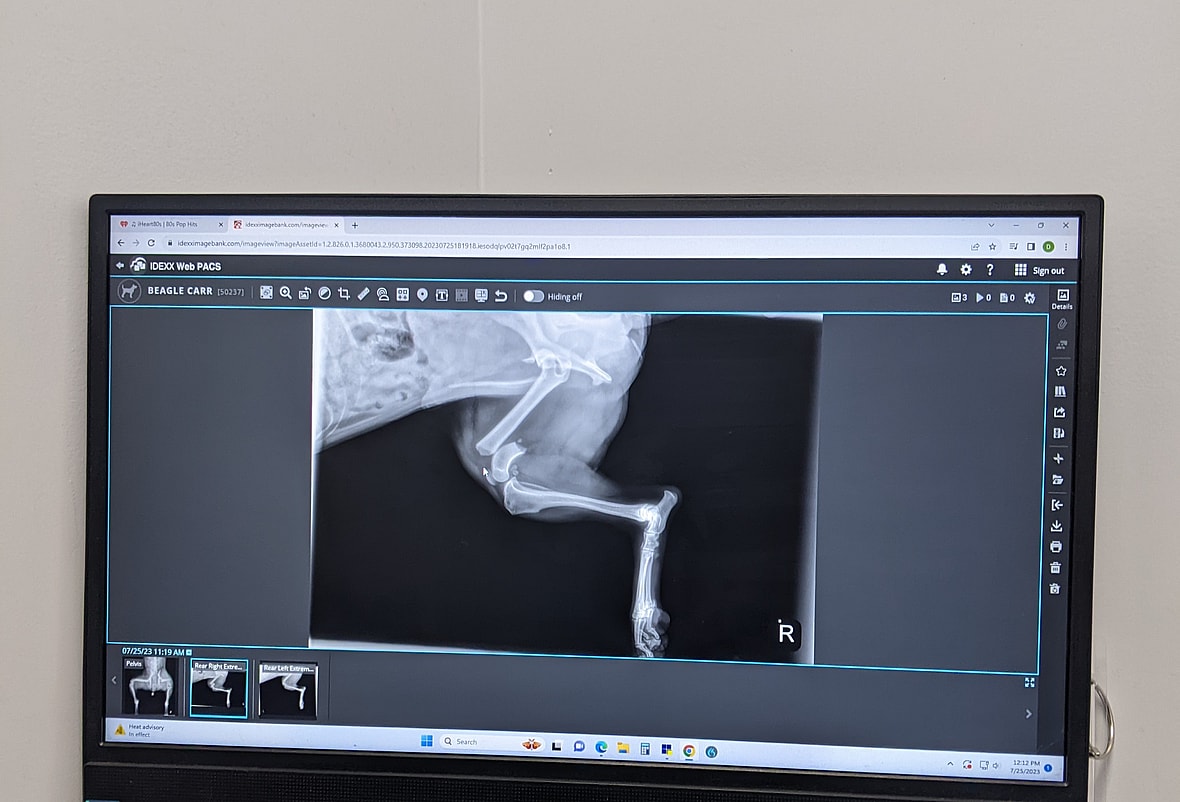

Sadly, Cruiser and two other stray dogs were hit by a car while living on the street. The other two dogs had already passed when a good samaritan stopped to help, but they were able to get Cruiser to a nearby veterinarian. There, vets found that he sustained several major injuries, including a broken hip, fractured right rear leg, and urethrorectal/perianal fistula (abnormal passageways developing between the urethra and the rectum). While the kind person who brought him in couldn’t afford the treatment for his veterinary care, they did contact Beagles and Buddies in Apple Valley, California, to help.

Someone from the nonprofit was able to pay for his surgery ($7000 including their discount for being a rescue), stay with him overnight, and then transfer him to the rescue to recover. They were given two options when it came to his shattered hip and broken leg–to amputate or to do reconstructive surgery. They opted for femoral head ostectomy surgery and placed a metal plate on his leg. With enough downtime during recovery before physical therapy, they believed Cruiser would retain mobility in his leg. And they were right!